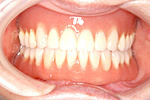

② 前から見た状態・治療前

⑤ 上下とも治療の終わった状態。メインテナンスに入ります。

60才代 女性

総額:360万円(税別)

治療期間:約1年

リスク副作用:経年的な骨の吸収。セラミックの破損。